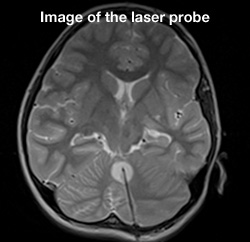

Laser ablation brain surgery

On May 29, 2013, Cook Children's became the first pediatric hospital in North Texas to perform iMRI-guided laser ablation brain surgery. For the patient, it was a triple win. He was the first to undergo this surgery, and the first at Cook Children's to have this surgery for epilepsy. But the biggest win of all was that just 24 hours after the surgery, the patient was seizure-free and discharged from the hospital. Being the first to perform this surgery wasn't the only benchmark we set that day. We raised the bar on more effective treatment for kids with epilepsy and brain tumors.

Thanks to this minimally invasive surgery, children, teens and young adults no longer have to undergo a craniotomy, or open brain surgery, for certain types of epileptic lesion or brain tumor procedures. And because tumors and lesions are removed by laser without cutting, the level of risk is greatly minimized and the positive benefits of surgery are greatly maximized. Best of all, because the surgery is so minimally invasive, patients can often return home within one to two days of their surgery. Recovery time can also be shortened so that ultimately the kids we treat can get back to business of being kids.

Currently, only 10 pediatric facilities in the U.S. offer this amazing surgery. Also known as stereotactic laser ablation, this iMRI-guided, minimally invasive procedure allows abnormal tissue to be thermally destroyed in real time. The surgery takes place in our iMRI suite, which reduces patient's surgery and anesthesia time and allows for targeted abnormal tissue removal, with little to no risk to surrounding brain tissue. Most patients go home within 24 hours and with only one stitch.

Laser ablation uses targeted light energy to destroy tumors and damaged tissue. Using guided iMRI technology, the doctors can see precisely where the tumor or lesion is in the brain and the laser energy can then be delivered right to the targeted area.

- A 3.2mm hole is drilled for cranial access.

- The patient is placed into the iMRI.

- The surgeon guides the laser into position using imaging and then thermally destroys the abnormal tissue.

- The laser applicator is removed and a stitch is placed to close the incision.